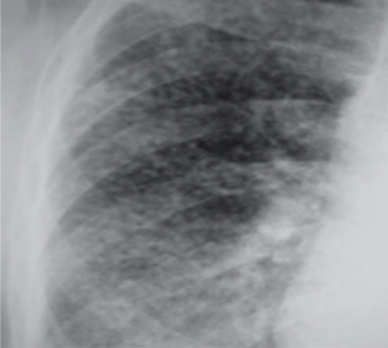

- Padrão Radiológico (OIT):

- Nódulos: Pequenas opacidades arredondadas (< 10mm), predominando nos terços superiores e posteriores dos pulmões.

- Peculiaridade: Tendem a poupar os seios costofrênicos (diferença crucial para asbestose).

- Silicose Complicada: Coalescência de nódulos formando grandes massas de fibrose (Fibrose Maciça Progressiva).